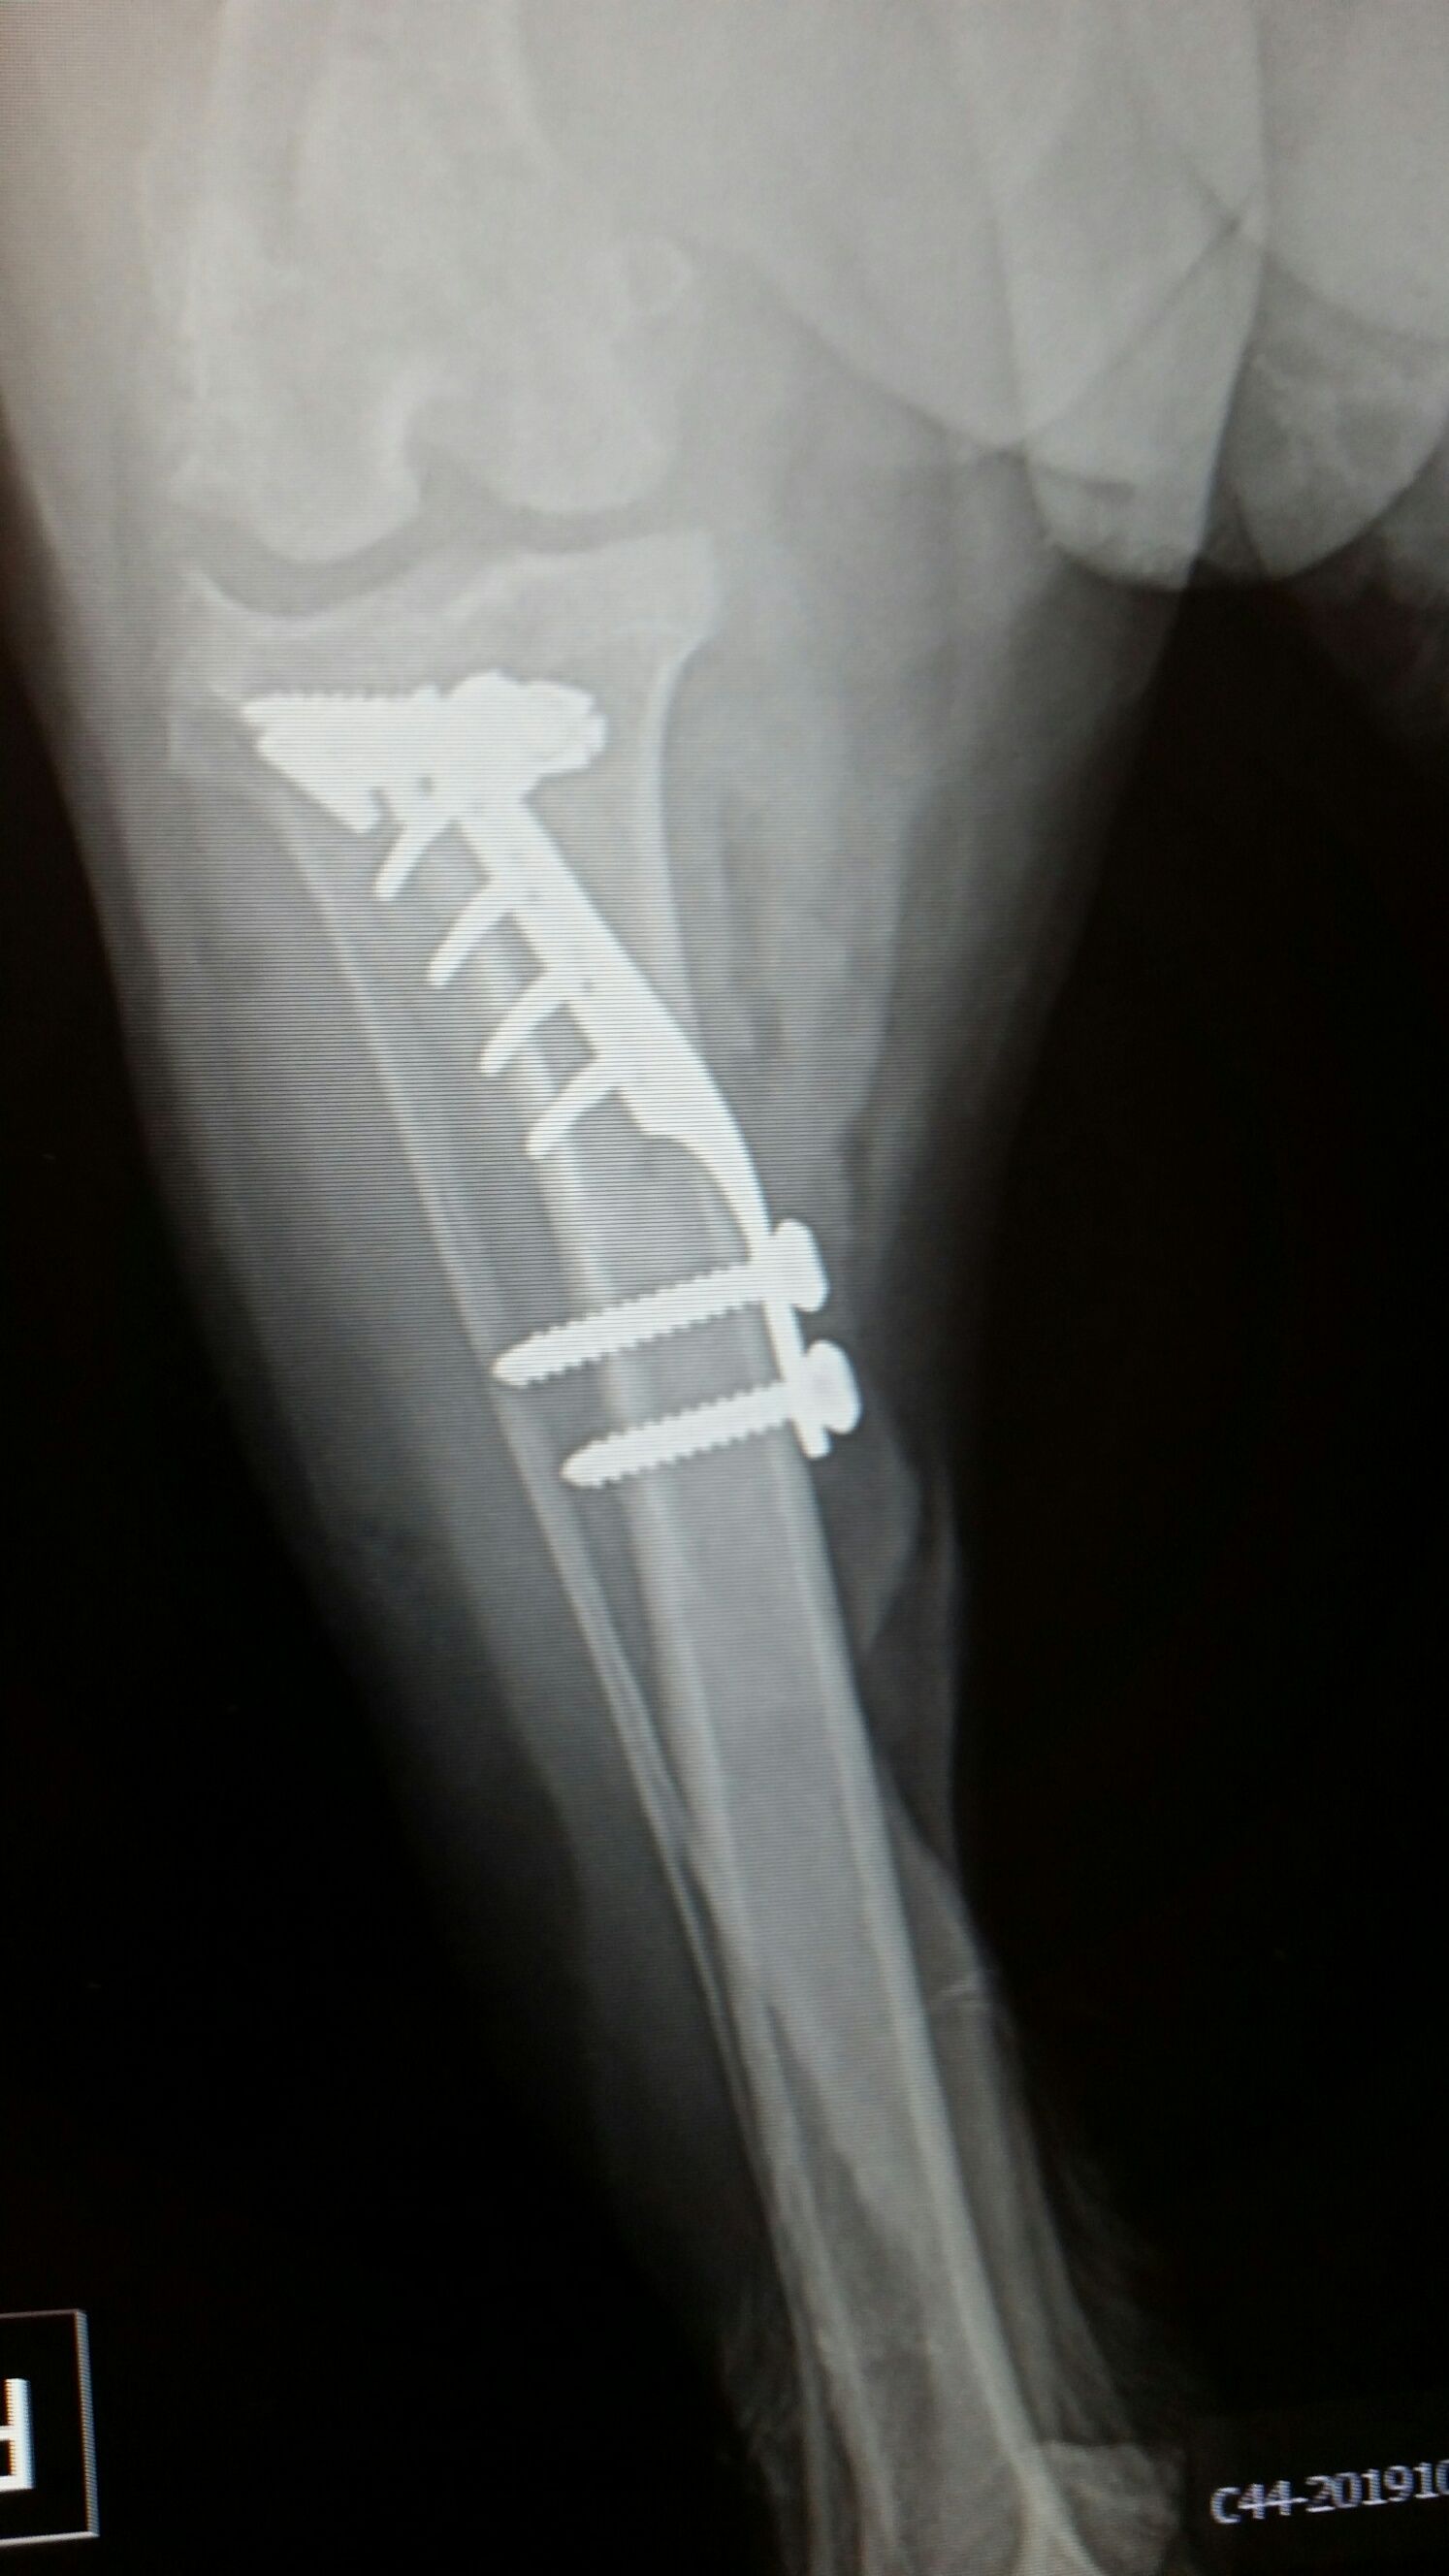

Thanks @beastielove ... Will be traveling to vet with "Bo" for 2 hours for Fentenyl patch removal which is stapled to her right hip...ouch. Thought my PCC friends might be curious as to what a TTA operation looks like (ACL replacement). PS: I do not go on vacations anymore, just visit vet's office for my relaxation).